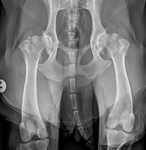

A new multi-year research project, led by the RVC, and in partnership with biopharmaceutical company UCB, will investigate potential novel therapeutic options and mechanism of disease progression in the ultra-rare genetic bone disease Sclerosteosis and the inflammatory condition Ankylosing Spondylitis, respectively. Although the cause of each disease is different, parallels can be drawn due to key pathologies being mediated by the growth of excessive bone in specific sites.

Sclerosteosis patients experience widespread bone overgrowth due to the loss of sclerostin expression, the body’s natural brake on bone formation. This can result in severe, and potentially fatal, pressure on the brain due to increases in skull thickness which can only be temporarily resolved through major surgery. Ankylosing Spondylitis patients experience bone overgrowth, most commonly in the spine, which can lead to pain, bone fusion and deformity. This is a major cause of structural tissue damage which can result in permanent disability.